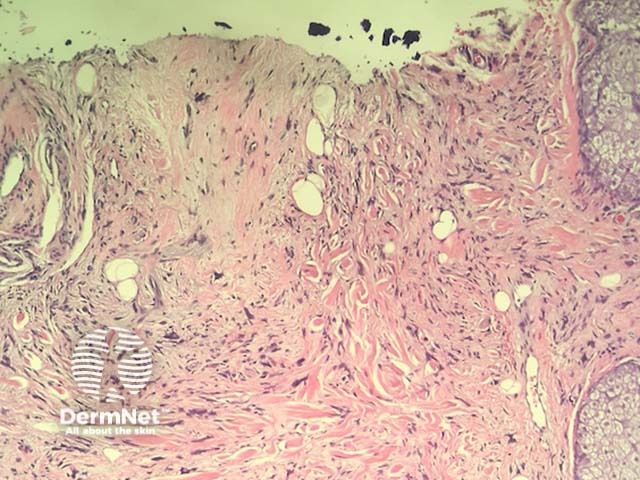

In neurofollicular hamartoma, the histopathology shows a nodular dermal spindle cell proliferation surrounded by prominent sebaceous glands. The spindle cells are plump or wavy. The sebaceous proliferation surrounds the mesenchymal component (figures 1–3).

Figure 1